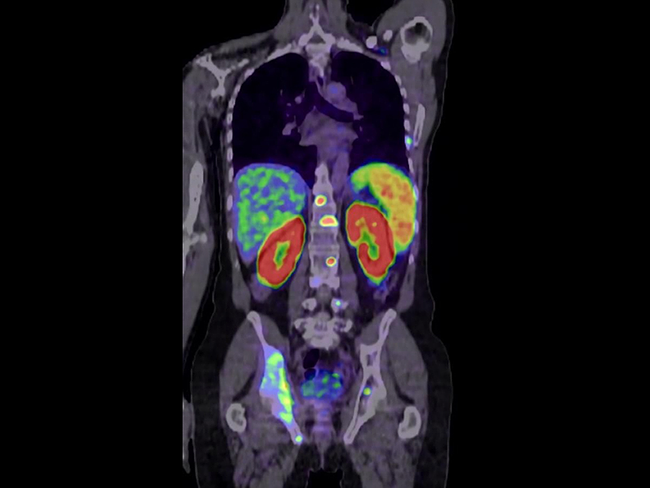

PET imaging

Radiopharm Theranostics Ltd.’s radiotracer RAD-101 met the primary endpoint in 92% of patients in the phase IIb imaging trial in brain metastases, according to interim results. To date, 11 of the 12 patients treated with RAD-101 (F18-Pivalate) achieved concordance with MRI (the primary endpoint) as assessed by PET imaging of brain metastases. The results showed significant and selective tumor uptake, and images confirm metabolic activity in brain metastases compared to equivocal MRI findings.

Radiopharmaceuticals, including 16α-18F-fluoro-17β-estradiol (18F-FES) PET/CT, are emerging as powerful tools with new diagnostic and therapeutic potential in breast cancer diagnosis and treatment, Han Sang-won, professor from the department of nuclear medicine at Asan Medical Center, recently told BioWorld.

The U.S. FDA’s approval of Telix Pharmaceuticals Ltd.’s kit for preparing prostate-specific membrane antigen-PET imaging for prostate cancer widens the opportunities for patients who live far away from large hospitals. The FDA’s nod for the imaging agent, TLX007-CDx, now branded as Gozellix, has a long shelf life and needs less equipment and preparation compared to some other agents.

After a second round, the U.S. FDA has accepted for review radiopharmaceutical company Telix Pharmaceuticals Ltd.’s BLA for its kidney cancer PET imaging agent, TLX250-CDx (Zircaix, 89Zr-DFO-girentuximab), granting it a priority review with a PDUFA date of Aug. 27, 2025.